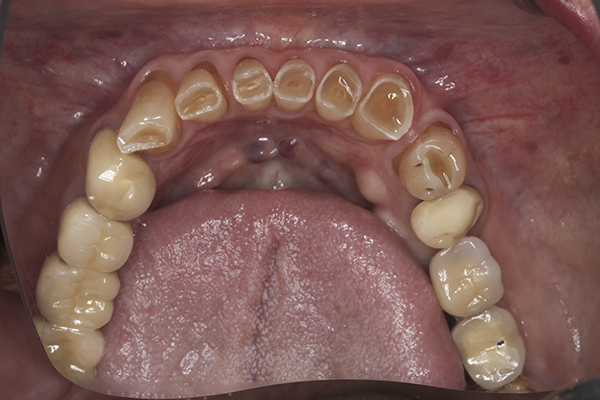

(15.) Preoperative maxillary, occlusal view.

Figure 15